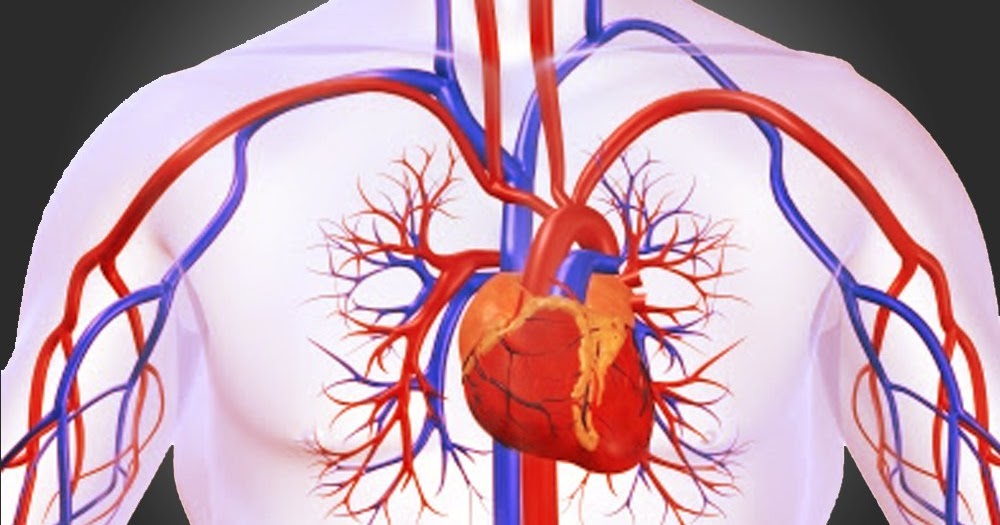

1 mengangkut sari sari makanan oksigen hormon ke seluruh tubuh. Pernyataan berikut adalah fungsi dari sistem sirkulasi atau peredaran darah pada manusia kecuali. Sistem peredaran darah berfungsi untuk mengangkut oksigen dan nutrisi keseluruh tubuh mengangkut sisa metabolisme ke organ ekskresi dan mengatur suhu tubuh.

Sistem peredaran darah besar istemik adalah sistem peredaran darah yang berasal dari jantung dan akan menuju organ organ yang berada di tubuh manusia secara keseluruhan kemudian akan di bawa ke jantung. K13 Revisi Antiremed Kelas 8 Biologi-Sistem Peredaran Darah Latihan Soal doc. Salah satu bagian darah yang memiliki peranan bagi pembekuan darah ialah.

99 Soal Sistem Peredaran Darah Manusia Pilihan Ganda Pembahasan Contoh Soal Sistem Peredaran Darah Manusia dan Pembahasan beserta Kunci Jawaban Sistem peredaran darah sistem kardiovaskular merupakan suatu sistem organ yang berfungsi memindahkan zat ke dan dari sel. Cek kumpulan materi soal-soal Kelas 11 Kurikulum 2013 Revisi SMA Sistem Peredaran Darah dan kunci jawabannya. Pada Soal PAT Biologi SMA Kelas XI meliputi KD sebagai berikut.